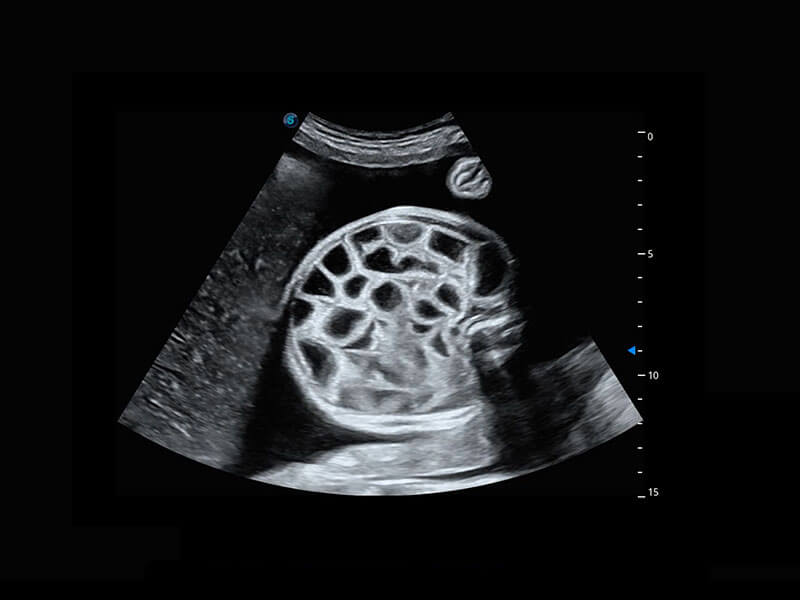

P60為盆底超聲檢查提供應(yīng)用方案,多種腔內(nèi)及腹部容積探頭提供從二維、三維到四維的優(yōu)異圖像品質(zhì),實時快速三維容積數(shù)據(jù)獲取,專業(yè)的測量工具包等人性化設(shè)計,為超聲醫(yī)生診斷提供有力保障。

Lev.Hiat A-r: 16.33 cm2

Lev.Hiat H-r: 53.70 mm

Lev.Hiat W-r: 43.96 mm

Lt-LUG-r: 24.16 mm

Rt-LUG-r: 19.94 mm

能夠簡化盆底檢查的操作流程,可在二維模式及三維成像模式下實現(xiàn)一鍵自動提取出標準切面、自動識別當前切面、自動測量,提升盆底檢查的高效性,同時也能讓青年醫(yī)生快捷的獲得準確的檢查結(jié)果。